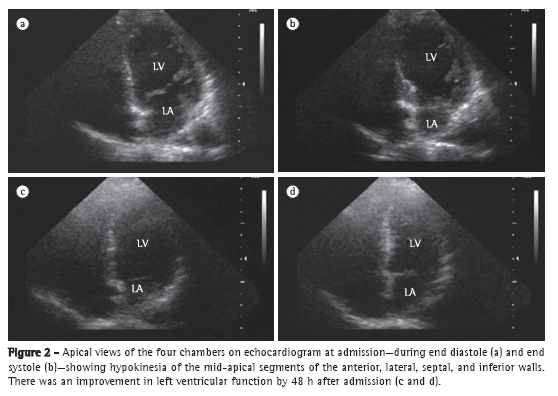

The electrocardiogram revealed sinus tachycardia with decreased septal QRS vector, intraventricular conduction disturbance, diffuse T-wave inversions, and corrected QT (QTc) of 543 ms (Figure 1). The troponin T peak and creatine kinase-MB peak were 2.5 ng/mL (normal value < 0.26 ng/mL) and 17.6 ng/mL (normal value < 3.6 ng/mL), respectively. The patient was treated as having high-risk acute coronary syndrome with acetylsalicylic acid, nitroglycerin, and intravenous heparin. Transthoracic echocardiogram with limited echocardiographic window showed hypokinesia of the mid-apical segments of the anterior, lateral, septal, and inferior walls (Figures 2a and 2b); ejection fraction of 25%; and diastolic dysfunction with impaired relaxation. The left ventricular (LV) configuration resembled the shape of a Japanese fishing pot with a rounded bottom and a narrow neck, used for trapping octopuses, known as a takotsubo, from which the term "takotsubo cardiomyopathy" is derived.

Six hours after admission, the patient developed cardiogenic shock. She was given large doses of catecholamines (dobutamine and noradrenalin), was submitted to endotracheal intubation, and required mechanical ventilation. She underwent emergency cardiac catheterization, which showed that her coronary arteries were normal. Cardiogenic shock reverted within 48 h, with an LV ejection fraction of 60% (Figures 2c and 2d). After a follow-up period of 2 years, she had normal LV function and QTc of 388 ms (Figure 1), without major adverse cardiac events.